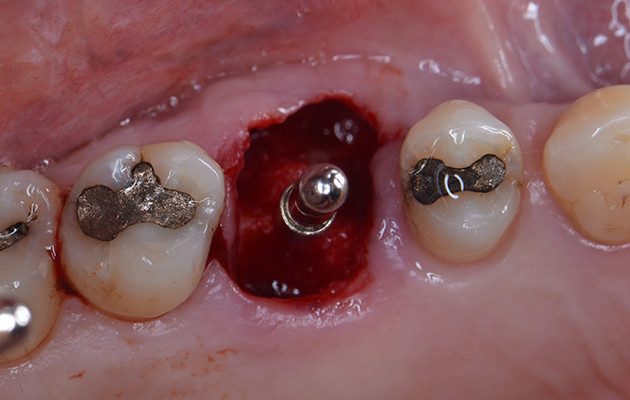

9 | Posição do Implante ao final da instalação.

10 | Preenchimento do alvéolo fresco com biomaterial substituto ósseo de origem sintética. Destaque para o Tapa Implante colocado para prevenir a entrada do biomaterial dentro do implante